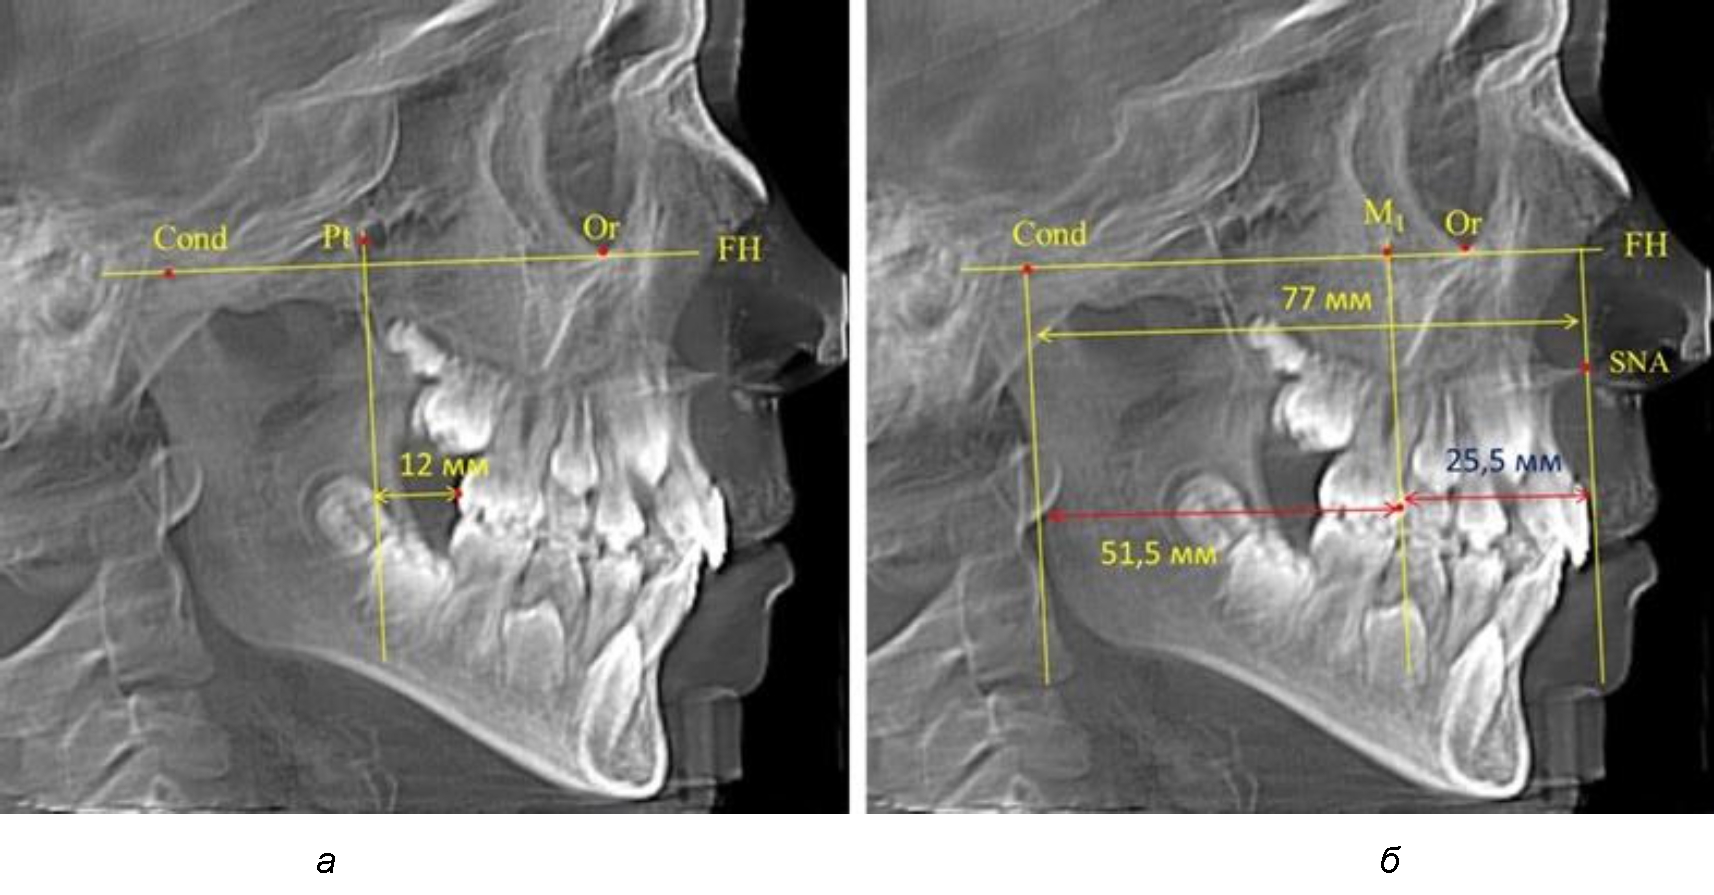

В то же время при увеличенном расстоянии от крыловидной вертикальной плоскости PTV до дистальной поверхности верхнего первого постоянного моляра, равное 23 мм, сагиттальный размер гнатического отдела составил 92 мм. При этом отношение кондилярно-спинального расстояния к кондилярно-молярному размеру (30,5), так же, как и при малых размерах, было близким к коэффициенту 1,5, что представлено на рис. 3.

Рис. 3. Особенности положения первых моляров по R. E. McDonald (а) и по предложенному методу (б) при увеличенном молярно-крыловидном расстоянии